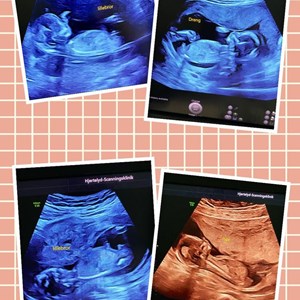

Hjertelyd - scanningsklinik for gravide

Fredagens sidste lille baby på briksen 🤓🩵 Han er ca 1200 gram i uge 28+1, og derfor meg...